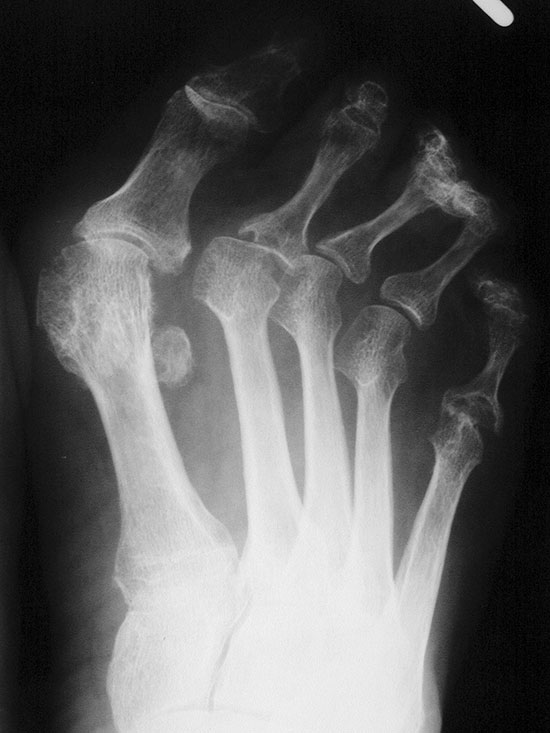

Konventionelle Röntgenaufnahmen sind das wichtigste bildgebende Verfahren. Die Aufnahmen zur OP-Planung sollten a.p. und streng seitlich im Stehen durchgeführt werden. Typische radiologische Veränderungen im Verlauf einer RA sind konzentrische Gelenkspaltverschmälerungen, gelenknahe Entkalkung, periartikuläre Weichteilschwellung, Erosionen der Gelenkflächen, später Zerstörung der Gelenkflächen mit Fehlstellungen sowie knöchernen Ankylosen oder Gelenkluxationen. Eine radiologische Stadieneinteilung erfolgt nach dem Schweregrad der destruierenden Veränderungen nach Larsen, Dale und Eek in 6 Stadien 3.

Dorsoplantare Darstellung des Vorfußes. Fortgeschrittene Destruktion des Metatarsophalangealgelenks am 5. Strahl und Lateraldeviation der Zehen.

Abbildung 4